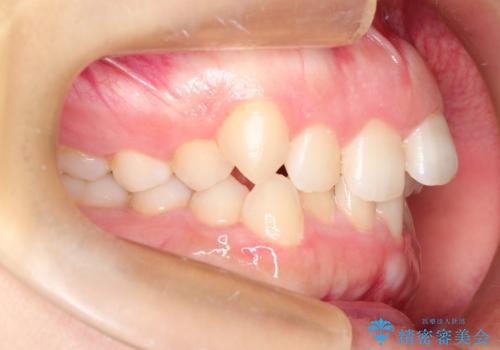

初診時の歯並びの状態としては、上下ともに全体に及ぶの中等度以上のがたつき(叢生)があり、全額的に歯列のアーチが内側に押しつぶされた状態でした。

強い叢生がありましたが、抜歯は行わず上下顎ともに、主に歯列弓の拡大を行い叢生を改善しました。